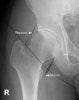

- Hip AP view

1) Alignment and Bones

① 내측 대퇴골의 아래에서 시작하여 목과 머리를 지나 돌기까지 근위부 대퇴뼈의 바깥면을 따라서 끊어진 것이 있는지 조사합니다.

② 체중을 견디고 일어설 수 있는 환자에서는 전위가 없는 골절의 확인을 위하여 원통형 AP view에서 뼈의 바깥면과 기둥선(trabecular line)을 주의 깊게 관찰합니다.

③ 전위가 없는 대퇴경부 골절의 경우 기둥선의 불연속선이 보일 수 있고, 박힘(impacted) 골절로 뼈의 밀도가 증가되어 보입니다.

④ 절구 관절면, 앞 뒤 가지의 피질선(cortical line)을 체크합니다.

⑤ 양측 볼기뼈는 좌우 대칭으로 보여야 합니다.